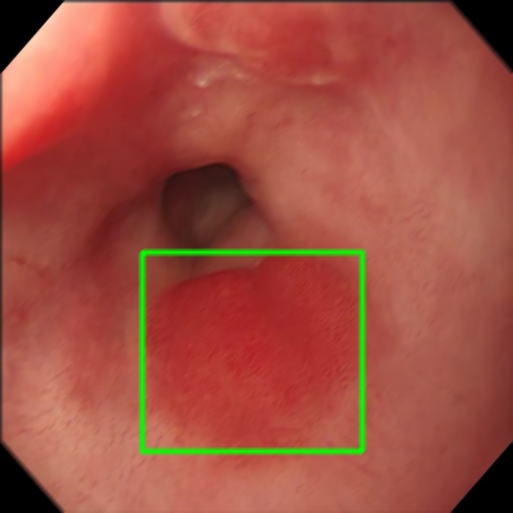

Motion Blur

Endoscopy GMAIMMbench Disease Diagnosis

Motion Blur - L0 (Original)

L0

L0 (Original)

Motion Blur - L1 (Moderate)

L1

L1 (Moderate)

Motion Blur - L2 (Severe)

L2

L2 (Severe)

Question

Observe the endoscopy image focusing on the area within the box. What is the most likely abnormality depicted in this section?

A barrett's esophagus B polyp C high-grade dysplasia D gastrointestinal tract cancer

Ground Truth: C. high-grade dysplasia